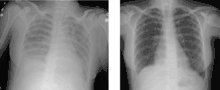

![]() مريض مصاب بمتلازمة الضائقة التنفسية الحادة ويُظهر تصوير الصدر بالأشعة السينية وجود عتامات الزجاج المصنفر مريض مصاب بمتلازمة الضائقة التنفسية الحادة ويُظهر تصوير الصدر بالأشعة السينية وجود عتامات الزجاج المصنفر | |

- وجود عتامات على جانبي الصدر (عند تصوير الصدر بالآشعة السينية أو بالتصوير المقطعي المحوسب) لا يمكن تفسيرها بأمراض الرئة الأخرى.

التصوير الطبي

لطالما كان التصوير الإشعاعي معيارًا لتشخيص متلازمة الضائقة التنفسية الحادة، وقد أكدت التعريفات الأصلية لمتلازمة الضائقة التنفسية الحادة على وجود نتائج علامات على الأشعة السينية حتي يكتمل التشخيص، وقد توسعت معايير التشخيص بمرور الوقت فصارت تقبل نتائج علامات التصوير المقطعي المحوسب والموجات فوق الصوتية كمساهمات متساوية، وتشمل نتائج الموجات فوق الصوتية التي قد توحي بوجود متلازمة الضائقة التنفسية الحادة كل مما يلي: